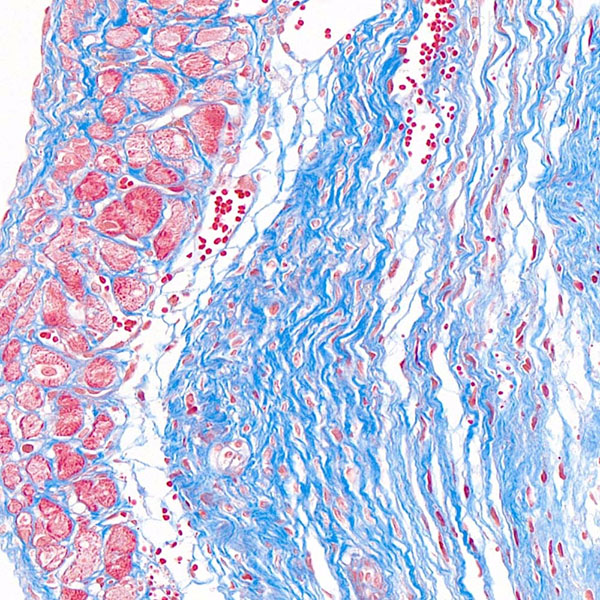

天狼猩红染色